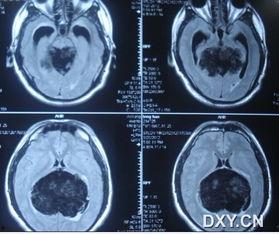

在很久以前,医生们只能通过X光片来观察肿瘤。那时的照片,黑白的,模糊的,就像是一幅抽象画。随着科技的发展,CT(计算机断层扫描)和MRI(磁共振成像)等先进技术逐渐取代了X光,使得肿瘤照片更加清晰、立体。

肿瘤照片对于医生来说,就像是一份密码。他们需要仔细观察照片中的每一个细节,从肿瘤的大小、形状、边界到周围组织的反应,这些都是判断肿瘤性质和制定治疗方案的重要依据。

还记得那些黑白模糊的X光片吗?如今,肿瘤照片已经进入了高清时代。CT和MRI等设备能够捕捉到更加细腻的图像,使得医生能够更加准确地判断肿瘤的位置和大小。